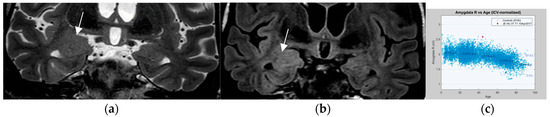

Postsurgical pathologic analysis of specimens of lesions missed by a negative brain MRI—even when performed using an epilepsy specific protocol—disclosed focal cortical dysplasia (FCD), hamartia, gliosis, and hippocampal sclerosis as the most common entities (Figure 1) [62].

Histologically confirmed FCD I depicted by abnormal deep and straight left. collateral sulcus with a slight blurring of the gray–white matter junction on the FLAIR image. (a) (1.7 mm) and signal hyperintensity of the cortical border. Reduction of adjacent parahippocampal white matter (white arrow on MP2RAGE sequence) (b) slice thickness 0.9 mm. The hippocampus displays a mild signal increase on the FLAIR image (without atrophy) as a sign of dual pathology. Both lesions were missed on prior 1.5 T examination in a patient with left temporal lobe epilepsy.

4.2. A Standardized Epilepsy Specific Protocol Provides Superior Diagnostic Yield

A comprehensive epilepsy-targeted MRI protocol is the key factor to identify, localize, and characterize an epileptogenic lesion (Figure 1). The neuroimaging task force of the ILAE advises the “Harmonized Neuroimaging of Epilepsy Structural Sequences” (HARNESS-MRI) protocol that encompasses three “core” sequences: iso-tropic submillimetric FLAIR and 3D T1 images and high-resolution 2D T2 sequences to be performed soon after the first seizure [64].